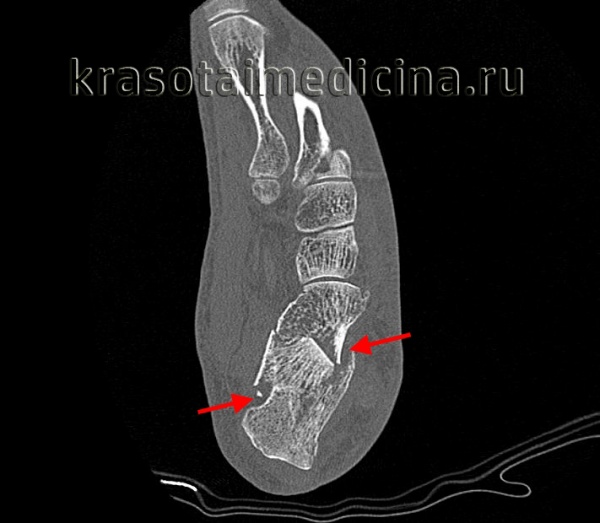

• На рентгенограмме стопы в боковой проекции на рис. 1 отмечается депрессия задней фасетки

• На рентгенограмме голеностопного сустава в проекции на синдесмоз на рис. 2 видно смещение наружной стенки пяточной кости и расширение за счет этого пяточной кости

- Предоперационная тонкосрезовая КТ обязательна и позволяет оценить характер внутрисуставного перелома (задней фасетки). На рис. 3 представлены КТ-срезы при оскольчатом переломе задней фасетки пяточной кости